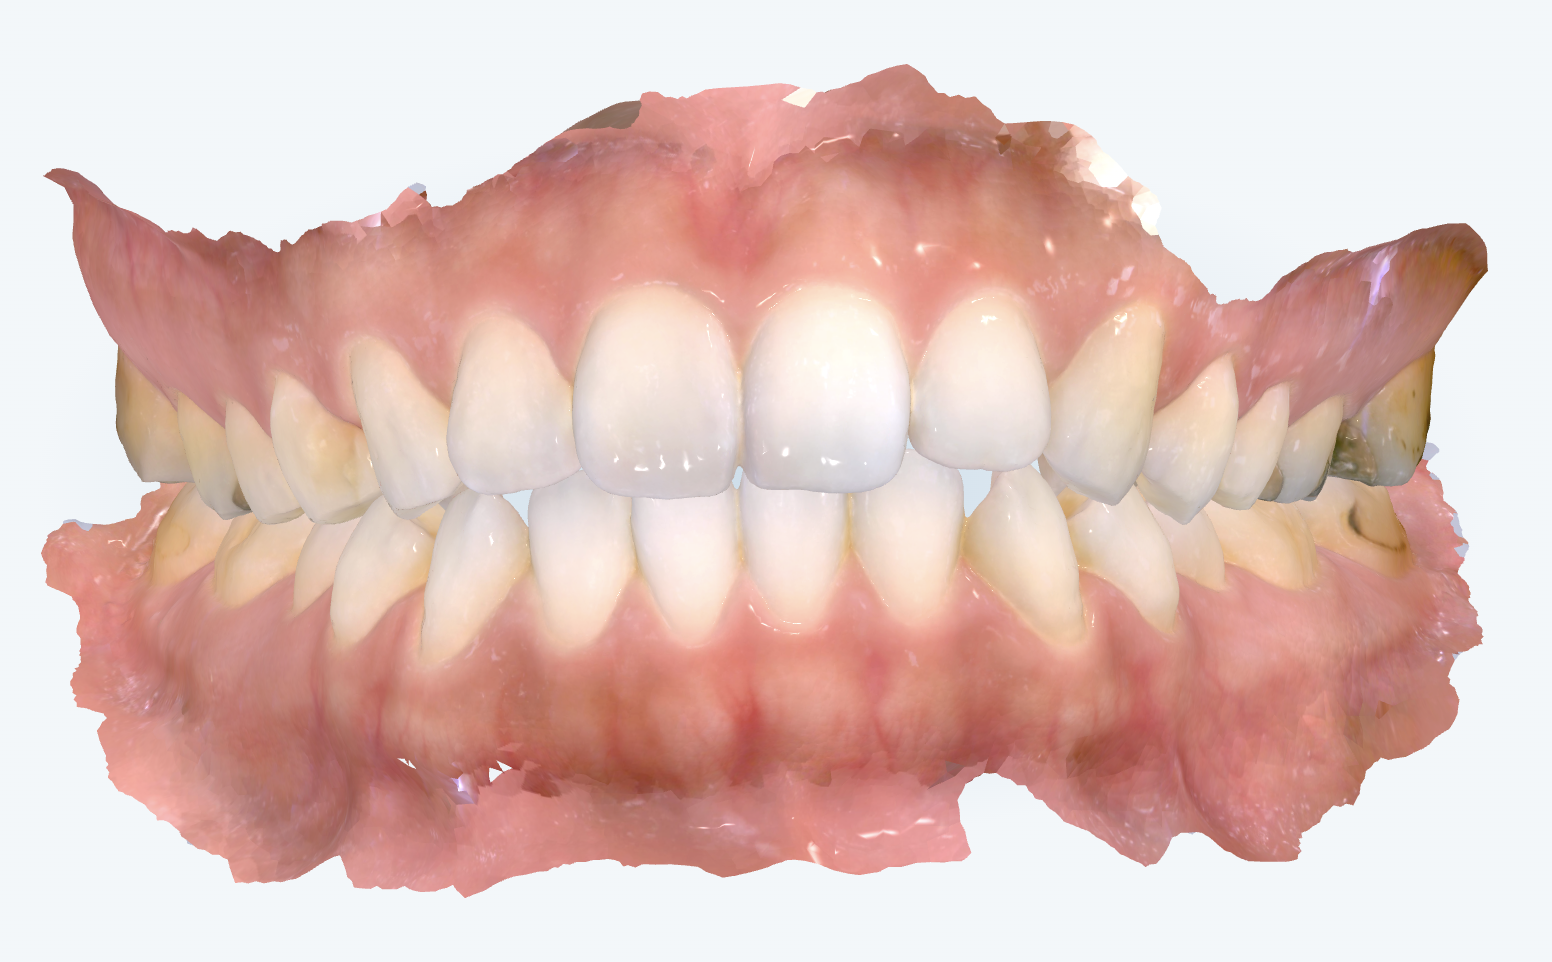

初診時の画像診断

奥歯の咬み合わせには、わずかに出っ歯の傾向がみられました。

上下の前歯が前方に位置しているため、口元が少し出た印象が見受けられました。